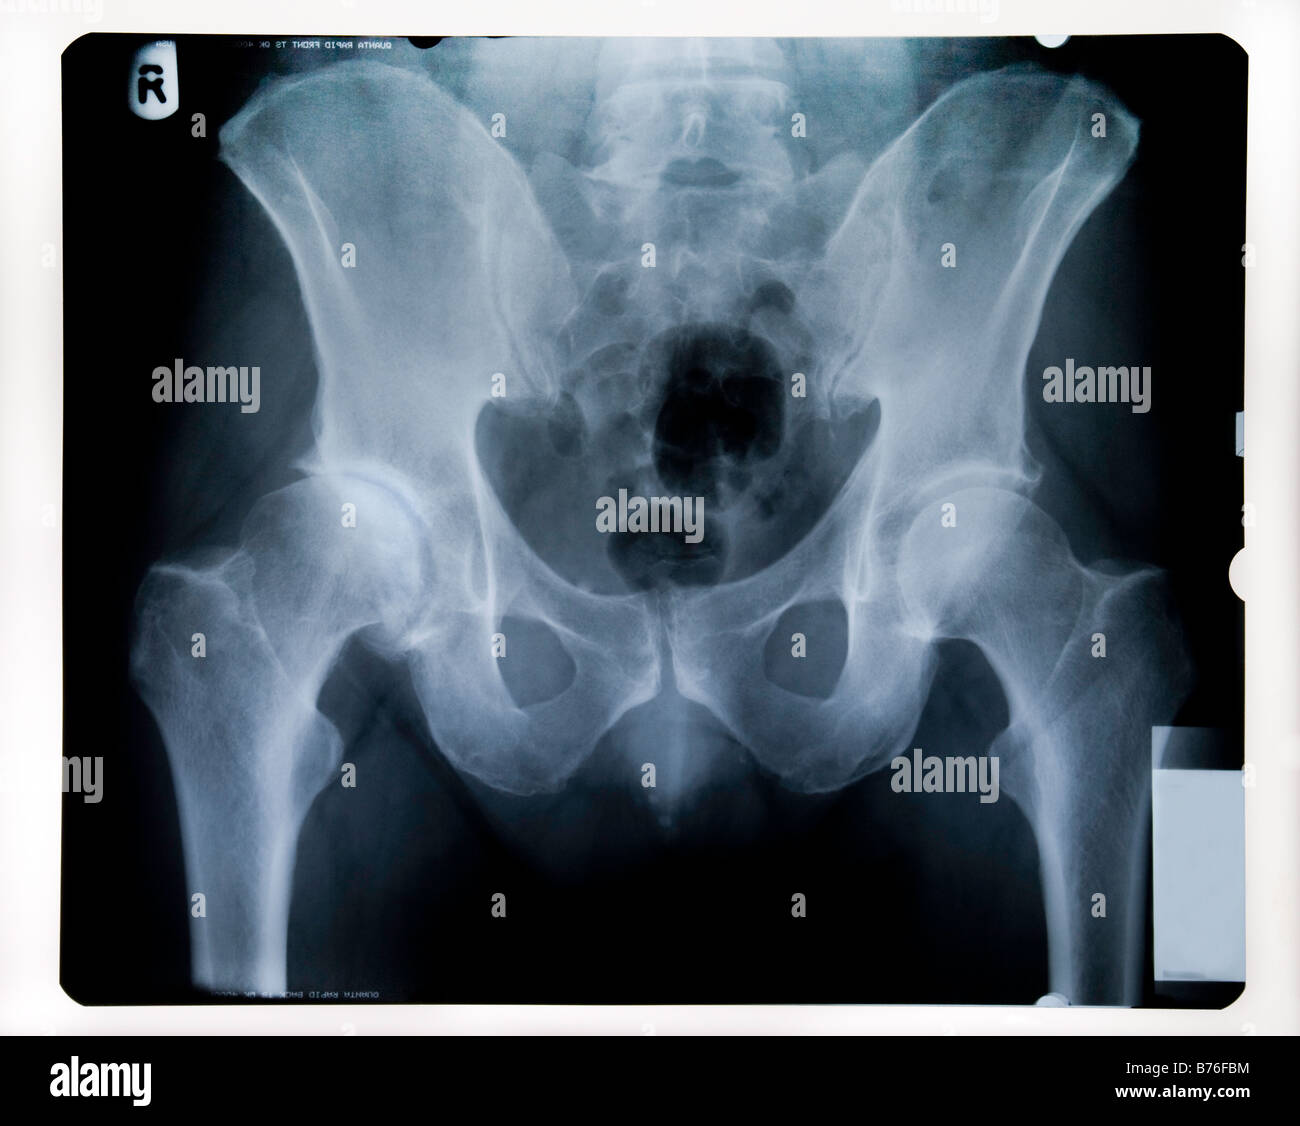

Hip Joint Xray View . The hip joint is a synovial joint between the acetabulum of the pelvis and the head of the femur, which connects the axial skeleton with. Suspected osteoarthritis of the hip) in an. The hip series is comprised of an anteroposterior (ap) and lateral radiograph of the hip joint. The dunn view is a radiographic projection of the hip that demonstrates and examines the hip joint, femoral head, acetabulum, and particularly the relationship of the femoral. Also shows unobstructed projection of sciatic notches and a profile image of acetabulum. This view provides a lateral image of The series is requested for a myriad of. Purpose and structures shown entire ilium, hip joint, proximal femur (femoral head within acetabulum), sacroiliac joint. This view assesses the hip joint for any potential fractures, dislocations, bone lesions or degenerative diseases (i.e.